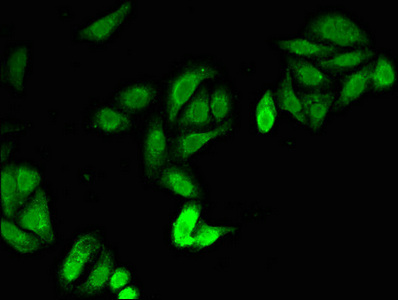

JAG1 Antibody (CSB-PA01949A0Rb)

驗證數(shù)據(jù)

Immunofluorescent analysis of HepG2 cells using CSB-PA01949A0Rb at dilution of 1:100 and Alexa Fluor 488-congugated AffiniPure Goat Anti-Rabbit IgG(H+L)